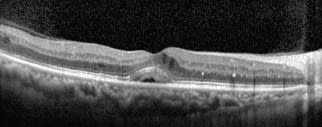

The patient was seen for follow-up 6 weeks after treatment. After just the single treatment, there was a significant reduction in the retinal thickness, from 326 µm to 272 µm. As expected, there is no scarring or other visible sign of the laser spots (Figs 3, 4). Although the edema was not completely resolved, the VA improved by 2 lines, from 20/50−1 to 20/25−2. The patient was pleased with the visual improvement. At a second follow-up 6 weeks later, the edema continued to resolve so we have not yet repeated the laser or given any additional Avastin injections.

Figure 3. 6 Weeks Post-MicroPulse Treatment: Central retinal thickness: 272 μm